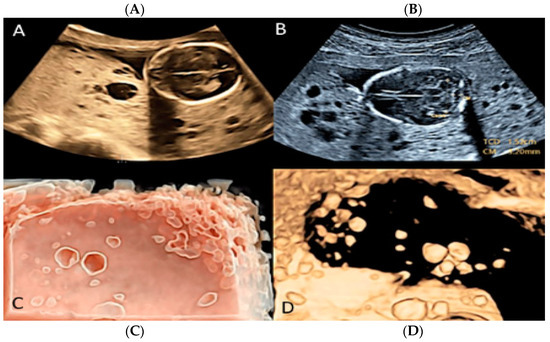

3.1.5. Placental Mesenchymal Dysplasia

3.1.6. Chorioangioma

- Quintana, R.L.; Baez, C.A.F.; Moraga, F.A.L.; Moraga, E.L.; Zepeda, J.H.G.; Leyva, F.; Manjarrez, R.E.A. Placental mesenchymal dysplasia, a rare pathology. Eur. J. Obstet. Gynecol. Reprod. Biol. 2019, 240, 122–138. [Google Scholar]

- Pawoo, N.; Heller, D.S. Placental Mesenchymal Dysplasia. Arch. Pathol. Lab. Med. 2014, 138, 1247–1249. [Google Scholar] [CrossRef]

- Psarris, A.; Sindos, M.; Kourtis, P.; Pampanos, A.; Antsaklis, P.; Theodora, M.; Chondrogianni, M.E.; Morphopoulos, G.; Loutradis, D.; Daskalakis, G. Placental Mesenchymal Dysplasia: Ultrasound Characteristics and Diagnostic Pitfalls. Ultrasound Int. Open 2020, 6, E2–E3. [Google Scholar] [CrossRef]